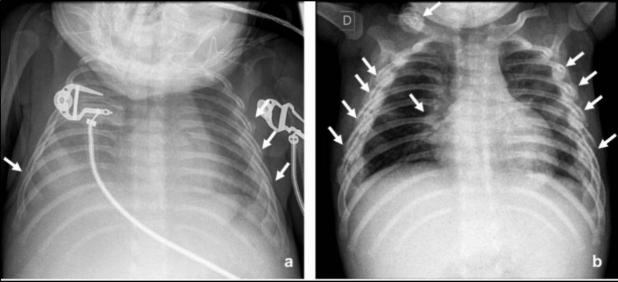

Se consideran fracturas altamente específicas de maltrato físico las costales posteriores y la lesión metafisaria clásica (fractura en esquina y en asa de balde) (Fig. 3)(10,14). Las fracturas costales en lactantes y niños pequeños se han relacionado con maltrato hasta en el 82% de los casos(11). En niños menores de 3 años, el valor predictivo positivo de las fracturas costales como indicador de maltrato es de un 95%(12).

En lactantes fallecidos por maltrato físico, las fracturas más comunes son las costales(13), que en ocasiones no son evidentes en la radiografía por no haber aún desarrollado reacción perióstica y callo óseo (Fig. 4) (13,14,15).

En lactantes o niños menores de 2 años con fracturas de huesos largos, la radiografía esquelética identifica fracturas adicionales hasta en un 10% de los casos(15). Precisar el tiempo de evolución de las fracturas es fundamental en la evaluación radiológica del maltrato. La formación de hueso subperióstico ocurre generalmente entre los 7 y 10 días; el callo blando se ve entre los 10 y los 14 días y la formación de callo duro entre los 14 y 21 días(10). Cuando el patrón de curación no concuerda con la historia aportada por los adultos, se debería considerar la posibilidad de maltrato (13,15).